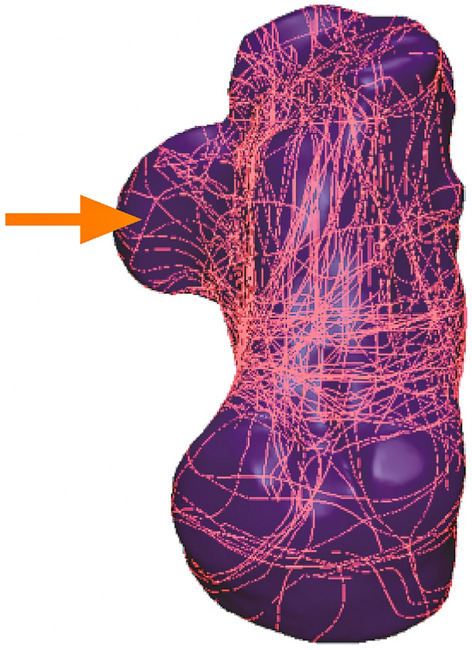

The method used for 3D CT mapping of sustentacular fracture. (A, B) Representative views of the 3D map of the 21 sustentacular fracture lines. (C, D) Representative views of the 60 patients without sustentacular fractures.

Figure 4.

3D maps

In each of the 67 patients, the fracture line was grouped on a typical calcaneal template, with separate fracture maps of the 21 patients with and the 60 patients without sustentacular fractures (Fig. 3A–D). In the sustentaculum tali, the majority of the fracture lines begin at the front of the sustentaculum tali, extending obliquely to the sulcus of the flexor halluces longus tendon (Fig. 4).

The sustentaculum tali are essential in maintaining the internal foot column, so conservative treatment may not be appropriate for displaced sustentacular fractures. Although the extensile lateral approach and tarsal sinus approach are most commonly employed for the operational treatment of calcaneal fractures17–20, the tarsal sinus method is gaining popularity17–20. One downside of this isolated lateral incision is that the sustentacular fragments cannot be managed directly, and the visualization of the sustentacular fragments is limited. Besides, the operation can only be accomplished through the surgeon's indirect experience to perform the reduction. And the flexor hallucis longus tendon may insert into the fracture line, resulting in a reduction complicated and leading to non-union21. In addition, sustentacular fractures are difficult to diagnose on lateral X-rays, hence misdiagnosis is common. Misdiagnosis and mistreatment of the sustentacular fractures can lead to severe issues, posttraumatic subtalar joint arthritis, fracture non-union, chronic impingement of the flexor hallucis longus tendon, paraesthesia of the medial plantar nerve, persistent pain and swelling of the medial hindfoot, progressive pes-planovalgus deformity or tarsal tunnel syndrome22,23. In this study, the 3D mapping of the sustentaculum tali revealed that the fracture lines start from the anterior of the sustentaculum tali, extending obliquely to the sulcus of the flexor halluces longus tendon. Consequently, the complexity of surgical reduction necessitated the consideration of introducing the flexor hallucis longus tendon into the fracture lines.